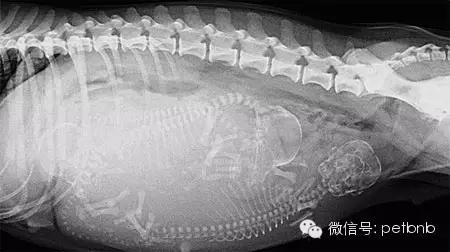

(孕后期的X光片,可以清楚看到狗宝宝和狗妈妈的骨骼)

通过X光或者B超可以清楚的看到狗狗孕育着几只狗宝宝。这样就不会发生主人以为狗狗已经生产完毕,但是其实还有小狗没出生的情况,这种情况通常会比较危险,母犬的体力耗尽,很容易疏于照顾,弄伤新生的幼崽。

难产风险比较高的狗狗,也可以清楚的看到母犬的骨盆大小和胎儿的头骨尺寸是否匹配,判断难产的可能性。